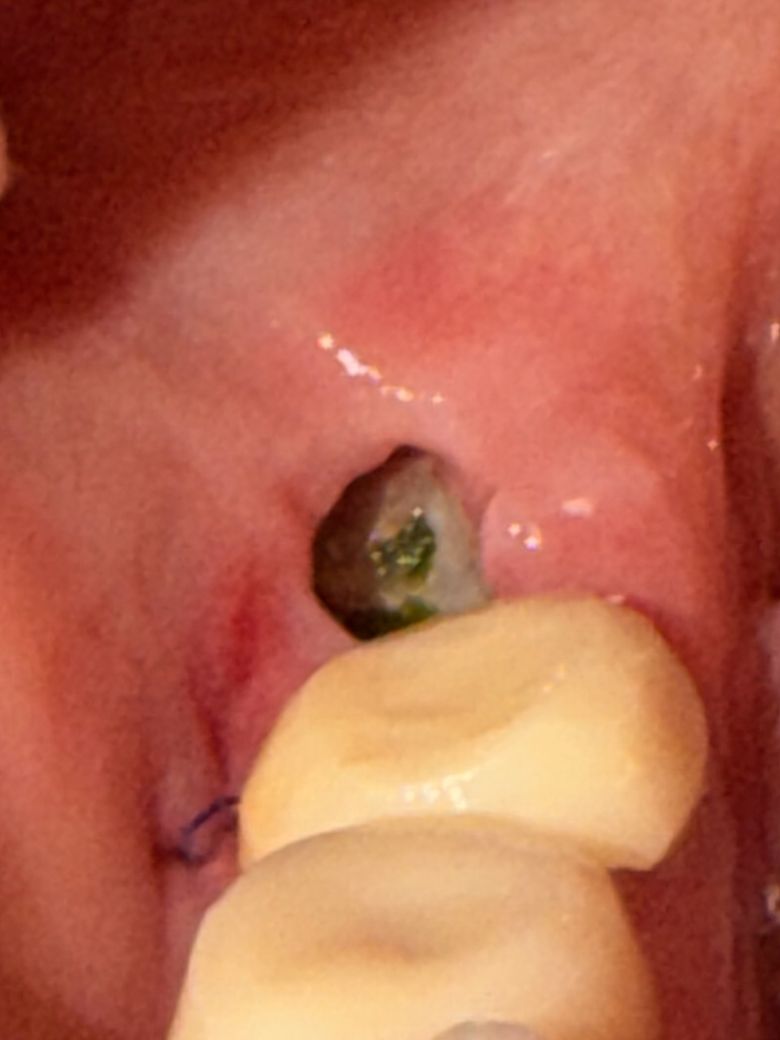

흰색이 차오르는 듯 하다 가운데 은색, 녹색? 빛이 나는게 갑자기 보이기 시작하는데 뭘까요..?

염증 냄새도 계속 느껴져요

어제까지만 해도 안보였는데 갑자기 보여요

• 2번 째 사진

사진 상으로는 해당 부위 식편(음식물) 들어간 것으로 보이며 고이면서 악취 생긴 것으로 추정 됩니다. 물양치 및 구강위생관리를 통해 음식물 제거해주시면 되며 스스로 관리가 잘 안될시에는 치과 내원하여 소독하는 것이 필요합니다. 더불어 봉합사 주변 식편 저류되면서도 악취 발생할 수도 있습니다. 큰 걱정은 안하셔도될것으로 보이나 꼭 물양치나 소독은 받으시기를 권유드립니다.

발치함부의 혈병을 제거되어 내부의 혈병에 덜 찬 것으로 보입니다. 크게 문제가 되진 않지만 해당 부위가 자극되지 않도록 주의하는 것이 좋습니다.

냄새가 심하게 난다면 드라이소켓 가능성도 있습니다. 일단은 이물질일 가능성도 있으니 가볍게 가글하면서 사라지는지 보세요